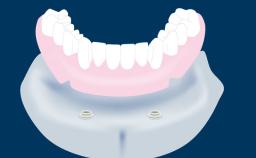

Fixed vs. Removable Prosthodontics for Restoring the Edentulous Maxilla

Fixed and removable prosthodontic implant therapy for restoration of the edentulous maxilla is both complex and challenging. Careful assessment and planning is needed in each individual case to explore whether a fixed or a removable solution will be the more suitable to satisfy the patient’s preference for optimal esthetics, phonetics, comfort and function. This Learning Pathway explores the prosthodontically driven treatment planning based on structured assessment, considered diagnosis and practical application in clinical case examples.